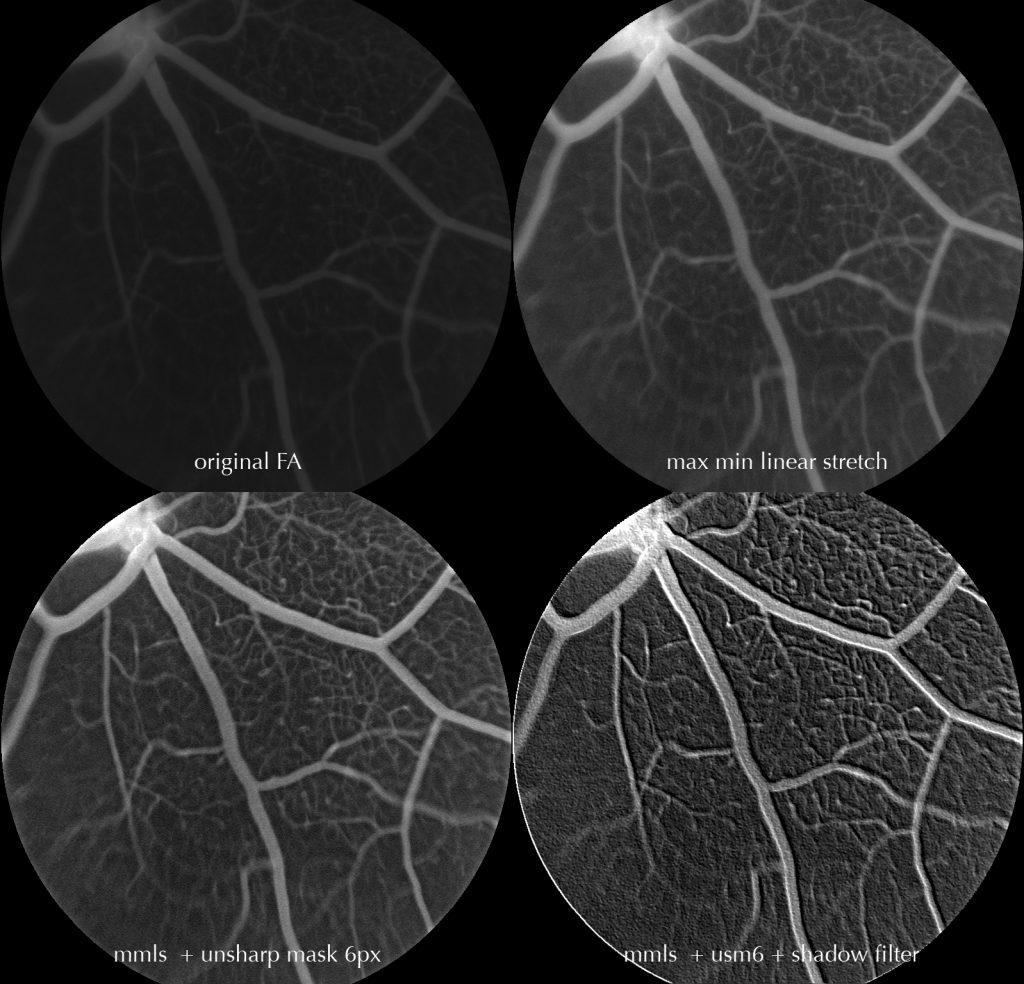

Upper left = raw FA image

Upper right = max min linear stretch (mmls)

Lower left = rmmls + unsharp mask 6px (usm6)

Lower right = rmmls + usm6 + shadow filter